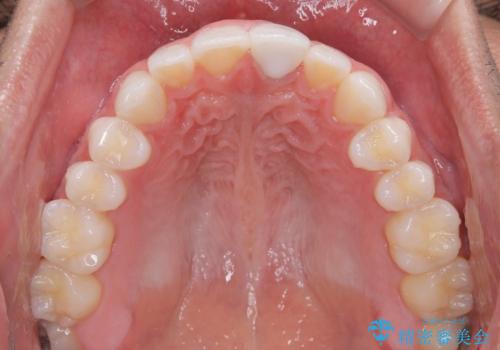

予想通り色と形の修正が多く必要となりましたが、最終的には納得のいく仕上がりとなりました。